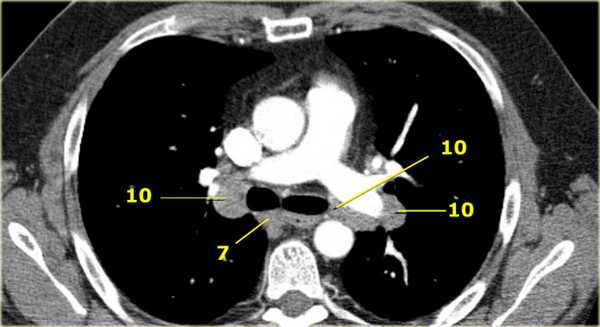

На ниже представленном постконтрастном КТ снимке представлен пациент с карциномой языка и лимфаденопатией II группы лимфатических узлов.

7. Подкаринальные лимфатические узлы

Эти лимфатические узлы расположены ниже уровня бифуркации трахеи (карины), но не относятся к нижнедолевым бронху и артерии. Справа они располагаются каудальнее нижней стенки промежуточного бронха. Слева они располагаются каудальнее верхней стенки нижнедолевого бронха. Слева лимфатический узел 7 группы справа от пищевода.

10. лимфатические узлы корня легкого

Лимфатические узлы корня расположены проксимальнее долевых узлов, но дистальнее медиастинальной дупликатуры и узлов промежуточного бронха справа.

Все лимфатические узлы 10-14 групп являются N1 узлами, так как они находятся вне средостения.